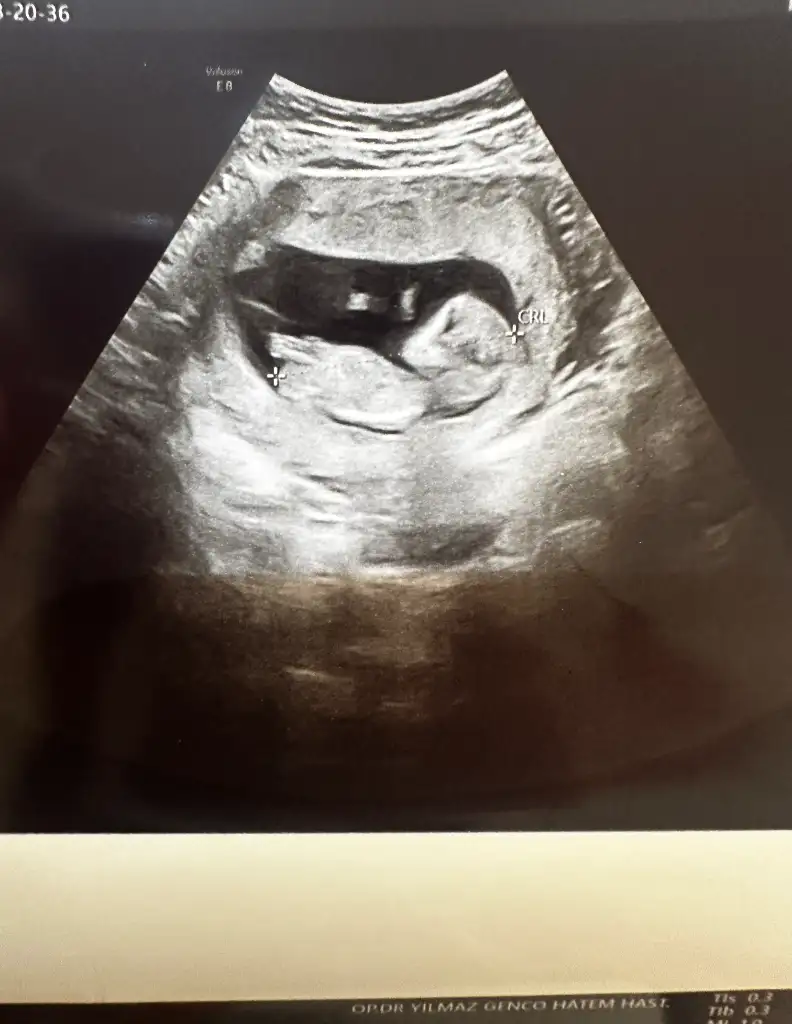

Bana da yorum yapar mısınız ? Arada gibi sanki erkeğin 1. Fotosuna da benziyor kızın 3.fotosuna da ben anlayamadımİnternetten nub teorisi diye arastır sende tahminde bulunabilirsin :)

Canım artık öğrenmişsindir cinsiyeti ne bebeğinin?Bana da yorum yapar mısınız ? Arada gibi sanki erkeğin 1. Fotosuna da benziyor kızın 3.fotosuna da ben anlayamadım

Erkek canımCanım artık öğrenmişsindir cinsiyeti ne bebeğinin?

Demek yuvarlak kese her zaman kiz degil)Bana da yorum yapar mısınız ? Arada gibi sanki erkeğin 1. Fotosuna da benziyor kızın 3.fotosuna da ben anlayamadım

Kese şekliyle ilgisi yok bence ama nub doğruDemek yuvarlak kese her zaman kiz degil)

Nub nasil oluyorki? Hala anlayamadim. 30 derecelik aciya gore dimi? Ben en son 10+2de ultrason muayenesinde oldum. Bi fark olur mu 2 haftada?Kese şekliyle ilgisi yok bence ama nub doğru